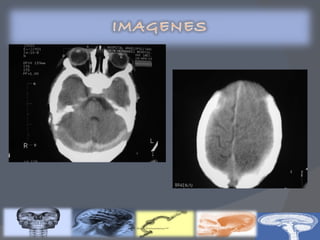

Recién nacidos con factores de riesgo : Prematuros Síntomas neurológicos Condiciones de riesgo  USG TRANSFONTANELAR (Primeros 5 días)

Clasificación de Volpe por ultrasonido transfontanelar Clasificación de Papile por tomografía axial computarizada Gravedad de la HIV Descripción GRADO I Hemorragia de la matriz germinal mínima(<10% del área ventricular) GRADO  II Hemorragia del área ventricular de 10 a 50% GRADO  III Hemorragia del área ventricular >50% Hemorragia intracerebral u otra lesión parenquimatosa Gravedad de la HIV Descripción % de HIV GRADO  I Hemorragia de la matriz germinal 40 GRADO II Hemorragia con tamaño normal de los ventrículos 30 GRADO III Hemorragia  con dilatación ventricular 20 GRADO IV Hemorragia ventricular, más parenquimatosa 10

GRADO 1 La hemorragia está localizada únicamente en la matriz germinal subependimaria GRADO 2 Contenido de sangre intraventricular que ocupa menos del 50% del área ventricular en una proyección parasagital GRADO 3 La sangre ocupa un área mayor del 50%, distendiendo el ventrículo Cuando existe una hemorragia intraventricular masiva que sobredistiende de forma muy importante los ventrículos laterales y, en general, todo el sistema ventricular está ocupado:tercer y cuarto ventrículos y espacio subaracnoideo de fosa posterior (cisterna magna)

Recién nacidos confactores de riesgo : Prematuros Síntomas neurológicos Condiciones de riesgo USG TRANSFONTANELAR (Primeros 5 días)

Clasificación de Volpepor ultrasonido transfontanelar Clasificación de Papile por tomografía axial computarizada Gravedad de la HIV Descripción GRADO I Hemorragia de la matriz germinal mínima(<10% del área ventricular) GRADO II Hemorragia del área ventricular de 10 a 50% GRADO III Hemorragia del área ventricular >50% Hemorragia intracerebral u otra lesión parenquimatosa Gravedad de la HIV Descripción % de HIV GRADO I Hemorragia de la matriz germinal 40 GRADO II Hemorragia con tamaño normal de los ventrículos 30 GRADO III Hemorragia con dilatación ventricular 20 GRADO IV Hemorragia ventricular, más parenquimatosa 10

GRADO 1 Lahemorragia está localizada únicamente en la matriz germinal subependimaria GRADO 2 Contenido de sangre intraventricular que ocupa menos del 50% del área ventricular en una proyección parasagital GRADO 3 La sangre ocupa un área mayor del 50%, distendiendo el ventrículo Cuando existe una hemorragia intraventricular masiva que sobredistiende de forma muy importante los ventrículos laterales y, en general, todo el sistema ventricular está ocupado:tercer y cuarto ventrículos y espacio subaracnoideo de fosa posterior (cisterna magna)